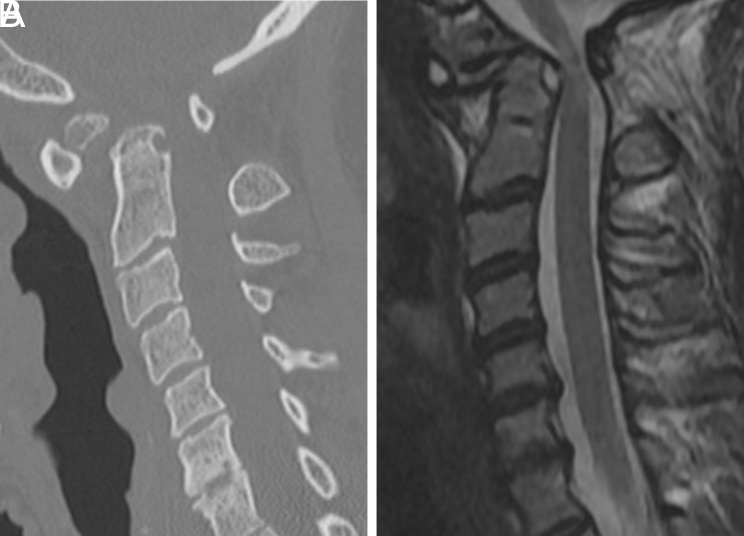

Vertebral arterial injury (VAI) remains a fatal complication of C1-C2 posterior screw fixation. Herein, we report asymptomatic bilateral VAI that was caused by screws following C1-C2 posterior fixation. A 34-year-old woman with cerebral palsy experienced quadriplegia after a fall. Cervical computed tomography (CT) showed increased ADI, with os odontoideum, for which C1 pedicle screw and C2 pedicle-lamina screw fixation were performed. Cervical magnetic resonance imaging (MRI) conducted for postoperative weakness in shoulder elevation demonstrated a well-decompressed spinal cord. However, neck CT angiography revealed bilateral vertebral artery (VA) violations by the C1 pedicle screw that induced occlusion of the V2 and V3 segments of both VA, with intact V4 segments. Diffusionweighted imaging showed no evidence of infarction. Cerebral angiography showed reconstitution of posterior circulation via the left fetal posterior communicating artery. Steroid treatment-induced improvement in shoulder elevation to the preoperative level, and no neurological deterioration has been detected for 3 years postoperatively. Prevention of VAI is one of the most important objectives when performing posterior cervical screw fixation. The screw should be inserted considering the rotation of C1 and C2. Notably, variations in cerebral circulation, which enable collateral blood flow to the posterior circulation, can lead to different sequelae in patients with iatrogenic VAI.